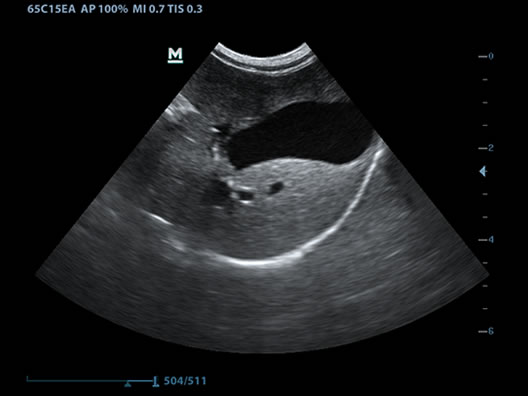

iScape™

Get a complete and extended view of the anatomical structure through panoramic imaging coupled with velocity indication and forward/backward scan ability making scanning much easier, smoother and more controllable.